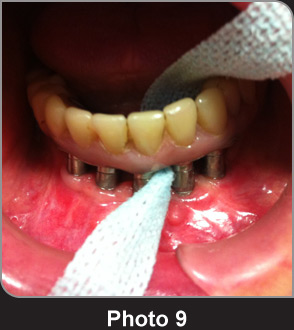

寬牙線X-Ribbon?用于清潔種植齒橋的案例。 寬大的粗紗布條圍繞牙齒和齒橋表面進行清潔極其有效。

寬牙線X-Ribbon?用于清潔齒橋,粗紋理的材料可以“抓住”斑塊和牙垢進行徹底清潔。